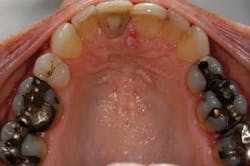

Full arch, occlusal images, as part of a photographic series, are an important adjunct to the new-patient examination. Images of only one or two teeth, such as those commonly captured with an intraoral camera, center on single-tooth dentistry but do little to help clinicians, staff, or patients think about patient needs in a comprehensive fashion (Fig. 1). The way clinicians evaluate and communicate with patients should be in alignment with the way they wish to treat their patients. Patients can better understand their needs when they can clearly see the "big picture." Full arch, occlusal images are an excellent way to help patients see the big picture and should be part of any new-patient examination (Figs. 2 and 3).